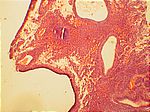

Gland. zyst. Hyperplasie, HE